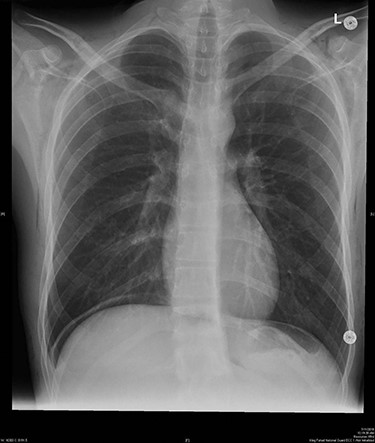

The surgeon was informed about the hypercarbia and desufflation. When examining the patient, the subcutaneous crepitus was found to be reaching up to the neck. Arterial blood gas confirmed respiratory acidosis (pH, 7.23; PaCO2, 56.1 mmHg; HCO3, 23.2 mmol/l; PaO2, 524 mmHg). About 15 min later, the CO2 level started decreasing until it reached 45 mmHg. Approximately 4 hours since the start, the operation was completed, and the patient was fully awake with stable vitals and the CO2 level below 45. Bedside lung ultrasound was immediately performed to exclude pneumothorax. Chest radiography was performed before extubating the patient, and bilateral surgical emphysema in the subcutaneous tissues of the chest and root of the neck was noted. Pneumothorax and pneumomediastinum were excluded (Fig. 1).

Bilateral surgical emphysema at subcutaneous tissues of the chest and root of the neck was found.